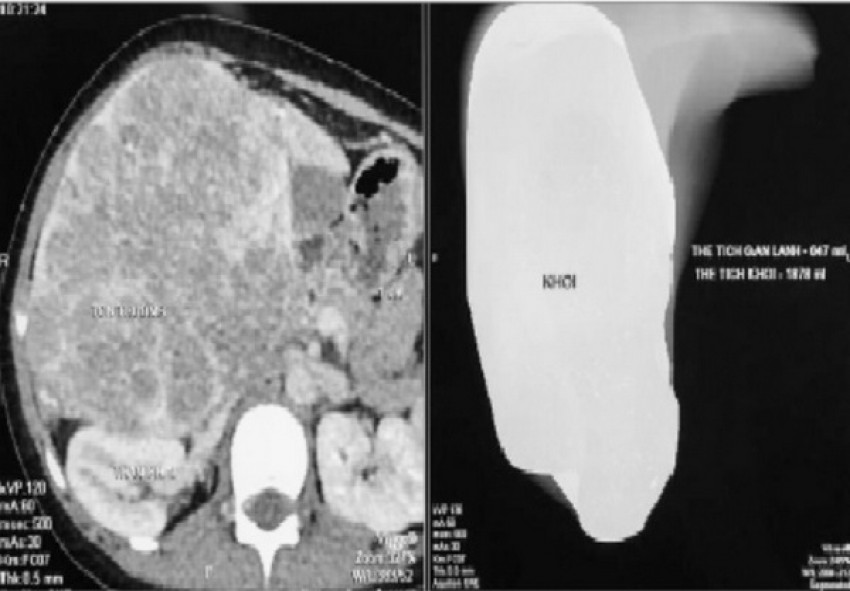

Khi trẻ bị viêm nhiễm như: viêm đường hô hấp, vi khuản trên đường hô hấp sẽ đi xuống đường ruột, có thẻ gây tiêu chảy và đau bụng. Do vậy, trẻ đau bụng và sốt thì cần đi khám ngay để chẩn đoán chính xác nguyên nhân đau bụng ở trẻ nhỏ, bác sĩ có thể phải chỉ định một số xét nghiệm như công thức máu, xét nghiệm phân, siêu âm, chụp Xquang, hoặc có thể phải chụp CT ổ bụng,... Tùy theo nguyên nhân cụ thể mà hướng xử trí, điều trị sẽ khác nhau.